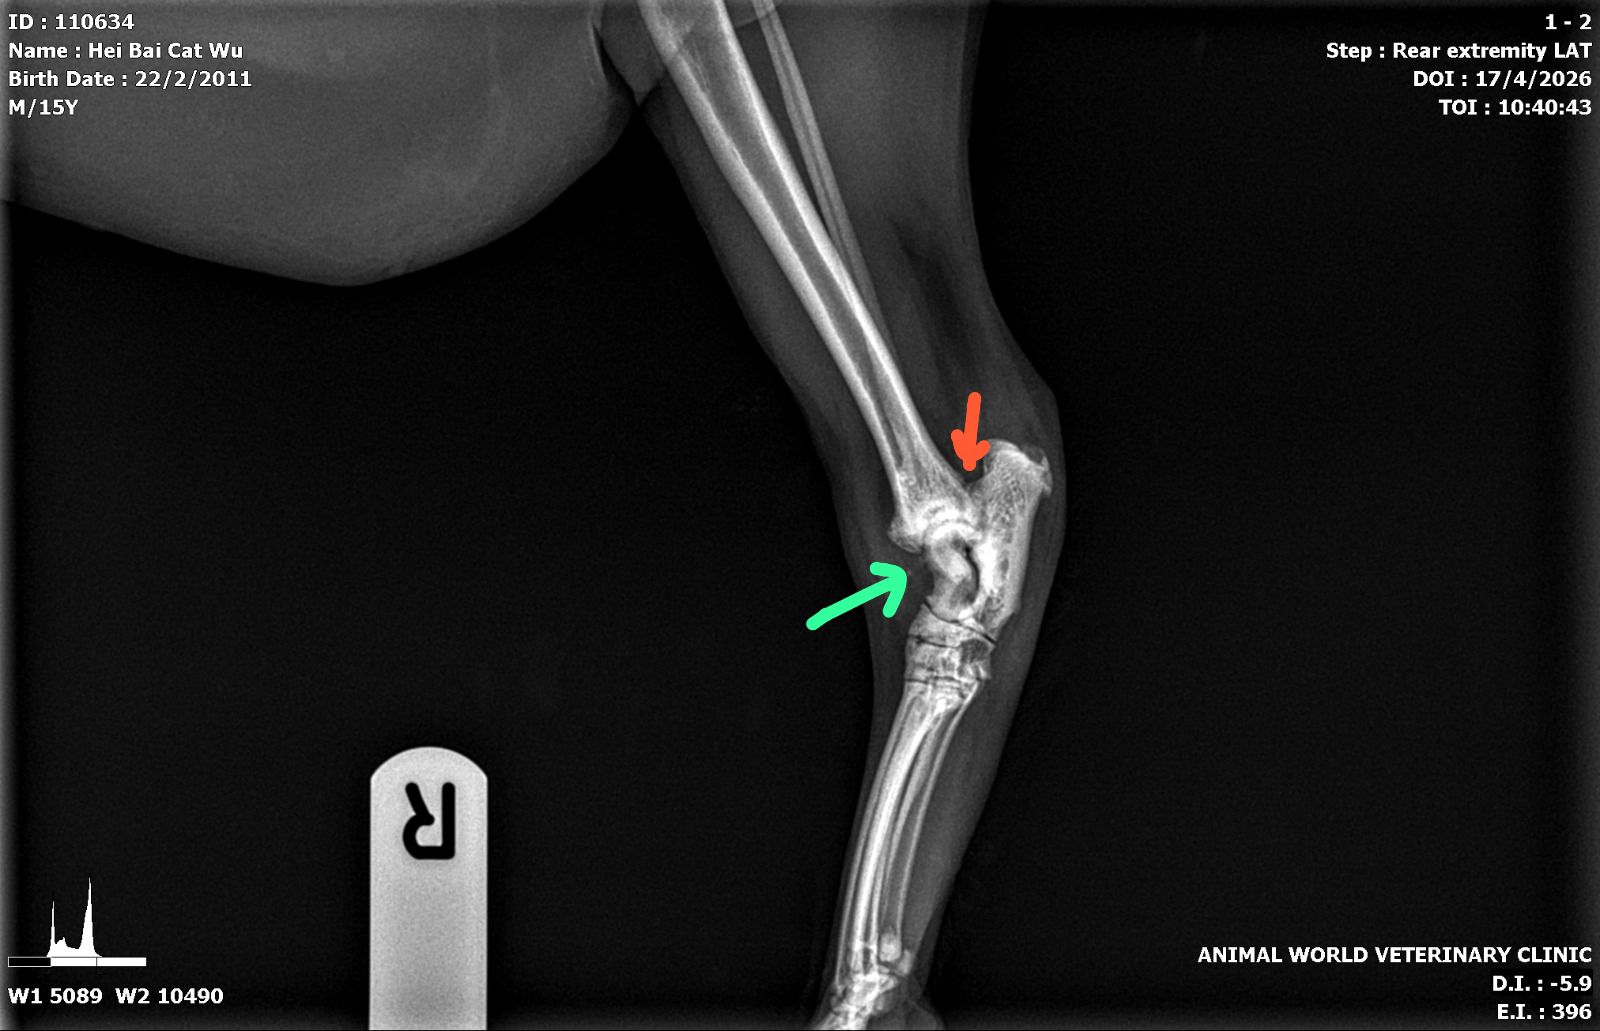

“Left hock

Green arrows – lots of osteophytes/arthritis

Red arrow – suspected fractured site but ideally need VD view

General bone density of hock bone more porous than usual”

“Right hock

Green arrows – osteophyte

Blue arrow – this lysis area in both legs”